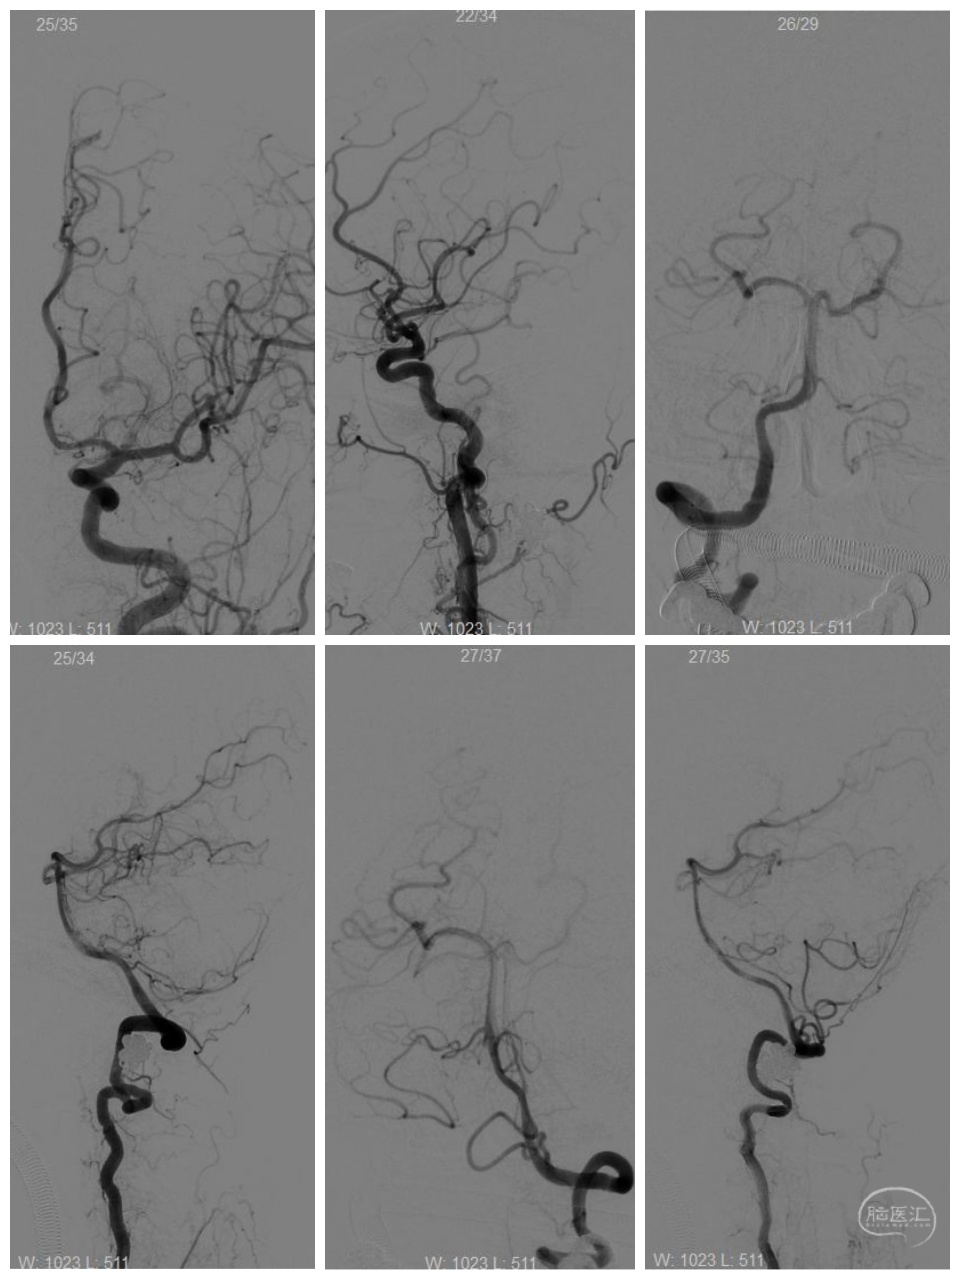

女性,66岁,突发剧烈头痛2小时。Hunt-Hess二级。

右侧颈内动脉-后交通动脉段分叶状动脉瘤。

正侧位

其他血管情况